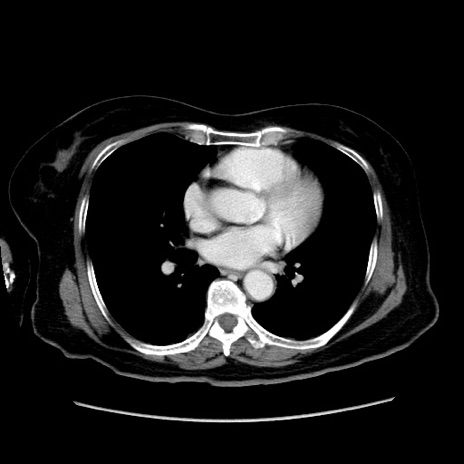

冠状断像

【症例】80歳代女性

【主訴】下腹部痛

【現病歴】約8時間前より下腹部痛の出現あり、救急外来受診。

【既往歴】両側付属器切除

【身体所見】意識清明、下腹部正中に手術痕あり、その部位に一致して圧痛と反跳痛あり。腸蠕動音は亢進。

【データ】WBC 9300、CRP 0.15